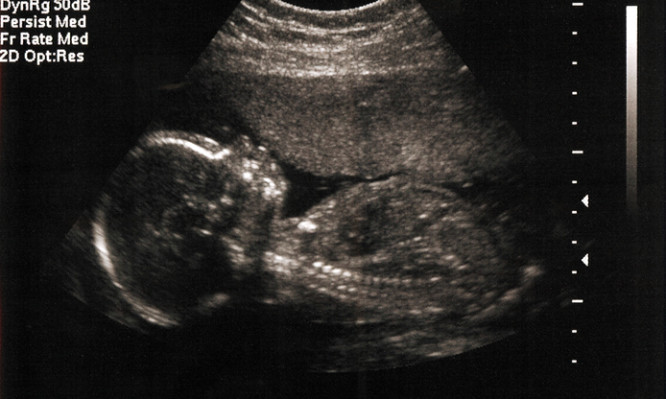

ΛΗΤΩ: Ένα σημαντικό βήμα για τον προγεννητικό έλεγχο της ανατομίας του εμβρύου στο 1ο τρίμηνο

Tη δυνατότητα αναγνώρισης σοβαρών προβλημάτων και διάγνωσης συγγενών ανωμαλιών δίνει ο έλεγχος των εμβρύων στις κυήσεις του 1ου τριμήνου,...